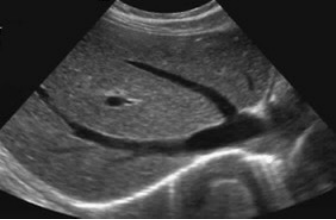

正常的肝在超声图像中呈现出均匀的低回声(类似灰黑色),就像一块质地细腻的绸缎,内部的门静脉、肝静脉等血管结构清晰可辨,走行自然流畅。而脂肪肝则截然不同:由于肝细胞内堆积了过量脂肪(主要是甘油三酯),超声波遇到脂肪颗粒时反射增强,肝在图像上会显得更亮高回声,医学上称为“肝回声增强”。

严重的脂肪肝患者,肝内部的血管结构会变得模糊不清,就像隔着一层厚厚的油雾观察,连肝静脉的分支都难以辨认。通过这种 “回声增强” 和 “血管模糊” 的特征,超声能快速筛查出脂肪肝的存在。

正常肝超声图

脂肪肝超声图